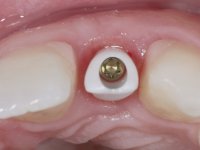

An impression was made on the implant with open tray technique using soft and regular consistency putty. At the laboratory, after confection of the work model, a diagnostic waxing was performed, which sought to find an aesthetic compromise solution. In this sense, a temporary workpiece screwed onto the implant was used to simulate the difficulties we would have with screwing the definitive work. This study abutment consisted of wax to reproduce soft and hard tissues, seeking to anticipate the use of ceramics of gingival and coronary shade. Also, part of the interproximal papillae corresponding to the distal portion of the 2.1 tooth and the mesial tooth of the tooth 2.3 were also waxed, anticipating the use of composite resin “chips” with gingival tonality. Finally, a veneer was waxed to correct the microdontia of the tooth 1.2. In this waxing, the vestibular emergence of the orifice for access to the screw of the implant abutment was evident. Once this therapeutic option was accepted, the implant abutment in polymerized composite resin was prepared at the lab, as well as the papillary "chips", also in composite resin of gingival tonality. Tested in the mouth, the abutment was screwed and the "chips" bonded. The access hole of the screw was filled with composite resin. In subsequent consultation, a gingivectomy was performed on the cervical contour of teeth 1.3, 1.2 and 1.1 with the aim of correcting the asymmetry between the first and second quadrant. After the soft tissues were cicatrized, a dental bleaching was performed according to the patient’s aesthetic requirements. Final impression on the implant was made using the silicone open tray technique, taking care to individualize the transfer piece by copying the emergence profile of the patient’s provisional abutment. At the laboratory, the impression yielded a definitive working model, on which the abutment was waxed on a plastic insert. This process was carried out with the orientation of a wall of silicone based on diagnostic waxing. The wax made on the plastic part was placed in a special holder that allowed its scanning in a laboratory scanner. This scan by CAD process informed the design of an abutment in Zr. later materialized by a CAM process. The Zr. abutment was tested in the mouth, validating its clinical and imaging establishment. During this consultation, the choice of color was made by the ceramist, of both the coronary ceramics and the ceramic of gingival tonality to be used. Individualized color scales were used. At the laboratory, the coronary and gingival ceramics were placed on the implant abutment and later, on a working model with refractory gypsum, a veneer of feldspathic ceramic was made. This veneer was built on a surface specially designed for this purpose in the abutment. This surface tried to reproduce a dental preparation performed for the same effect. In the mouth the abutment was screwed with a torque of 35N, the access hole to the screw was filled with Teflon and later filled with composite resin. The veneer was bonded onto the implant abutment using the conventional bonding technique, with relative insulation. For economic reasons, the patient did not proceed to perform the veneer on tooth 1.2. Although a limited aesthetic compromise was expected from the outset, a result was achieved which satisfied the patient.